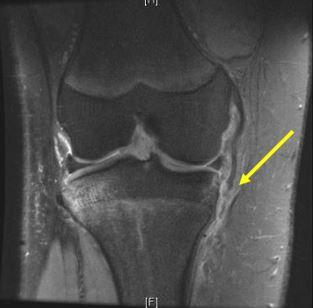

Injury to the medial collateral ligament (MCL) is the most commonly reported knee injury (Figure 2) and second only to concussion amongst all injuries in National Collegiate Athletic Association ice hockey players.8,39 The mechanism of injury typically involves a valgus force on the knee, which is often caused by collision into another player.39 Valgus stress testing with the knee in 30° of flexion is used to grade the severity of injury (Grade I: 0-5 mm of medial opening; Grade II: 5-10 mm of medial opening; Grade III: >10 mm of medial opening).39 One study that followed a single college hockey team for 8 seasons reported that 77% of injuries (10 of 13) occurred during player-to-player collision,39 with 5 being Grade 1 injuries, 6 Grade 2 injuries, 1 Grade 3; information was missing for 1 player. Nonoperative management of incomplete injuries, grade 1 and 2 sprains, with RICE and early physical therapy intervention to work on knee range of motion and quadriceps strengthening typically helps the player return to sport within days for grade 1 and 2 injuries to 3 weeks for grade 2 injuries. Complete tears have been managed both operatively and nonoperatively with evidence to suggest better outcomes after surgical intervention if there is a concomitant ACL injury requiring reconstruction.8,9

Figure 2. MRI of right knee of 16-year-old defenseman who sustained valgus blow to knee. The medial collateral ligament is torn distally and flipped above pes tendons, a Stener-like lesion.